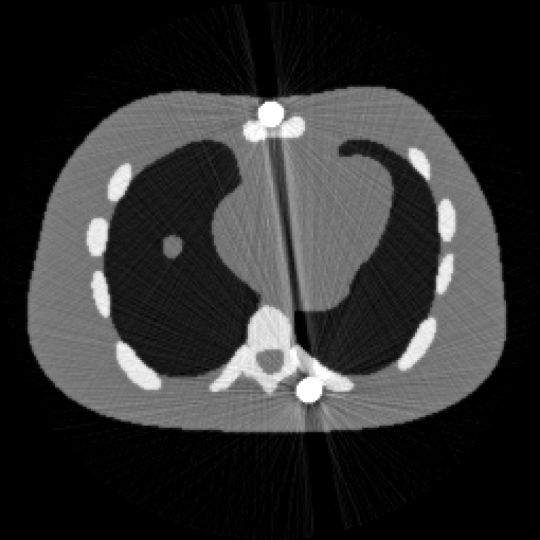

图1 含金属伪影的 NCAT图像 图2 校正后的NCAT 图像

正则化强化边界的对比度,引入图像的有界性约束进一步提升重建精度。基于全变差的预对偶形式,设计了两类有效且全局收敛的一阶原对偶算法求解上述非凸模型。大量数值实验结果验证了该方法的有效性(图1,图2),特别在预分割不准确的情况下,所提出的算法的重建精度得到显著提升。此外,所提出的全分裂算法比当前最具代表性的重加权JSR算法相比,计算速度平均提升两倍。